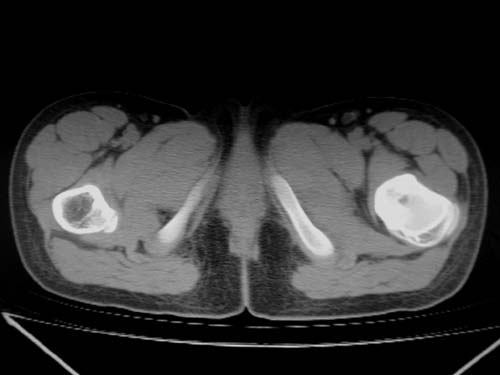

标题: CT19608:女12岁,左髋部疼痛,无发热病史 [打印本页]

标题: CT19608:女12岁,左髋部疼痛,无发热病史

左股骨干增粗,磨玻璃样改变——考虑骨纤维异常增殖症!

左股骨干增粗,磨玻璃样改变——考虑骨纤维异常增殖症!骨化性纤维瘤?